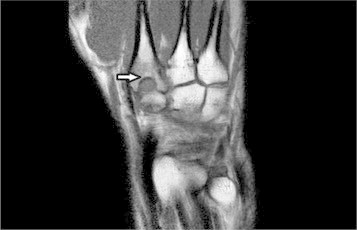

The radiograph of the right hand revealed a slightly expanded base of the second metacarpal with a cyst formation (Fig. 1). An MRI scan was arranged to rule out the possibility of any occult ganglions or an injury to the scapholunate ligament (due to previous surgery). The scan reported an abnormal second metacarpal base with profound oedema and focal area of bone irregularity and a sclerotic margin. A provisional diagnosis of a Brodie's abscess was suggested by the radiologist (Fig. 2). The inflammatory markers showed normal white cell count and CRP of 13.

Fig. 2.

MRI picture of the hand showing cystic lesion with well-defined margins suggestive of Brodie's abscess.